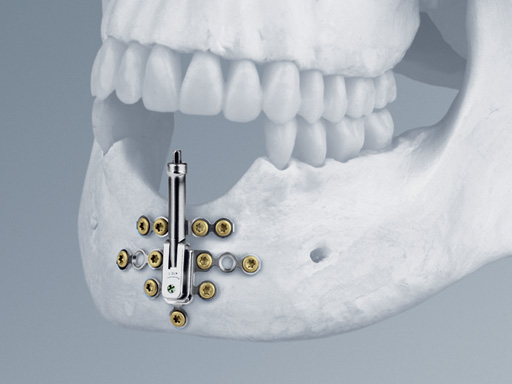

The new Alveolar Distractor is an internal distraction device intended for vertical bone augmentation of the alveolar ridge in the mandible and the maxilla with a deficit of in bony height and soft-tissue coverage.

• The lower body with angulation mechanism which is welded to the base plate

• The upper body with distraction mechanism consisting of a threaded rod as well as a threaded transport plate.

One of the main features of the Alveolar Distractor is its vector adjustability: an angulation mechanism allows easy intraoperative selection of the distraction vector. Therefore, extensive adaptations to the foot plates can be avoided. The distractor can be angled up to 52 toward the buccal and 32 toward the lingual side. After adjusting the vector, the angulation mechanism must be relocked by tightening the fixation screw.

The rigid base plate, with optional screw holes next to the angulation mechanism, allows safe anchorage of the distraction device in the residual bone segment. This leads to high stability ensuring rigidity and preventing potential unfavorable distraction vector changes due to soft-tissue pull.

Three different implant sizes allow for 8 mm, 12 mm, and 16 mm of distraction. This choice offers the flexibility to fit the distractor to different anatomical conditions. To achieve the desired distraction result, the two bodies are connected with a pin to change the plane angle of the bone plates in one dimension. The angulation mechanism allows for fixation of this angle. This feature allows for a single, individual intraoperative adjustment of the distraction vector and addresses the importance of a correct distraction vector in a sagittal plane.

The plate is extended vertically to improve the vertical stability of the system helping to withstand lingual and palatal soft-tissue tension and therefore also guarantees a stable distraction vector. This device has housing for the distraction body to prevent soft-tissue irritation as there is no exposure of the surrounding soft tissue to the threaded rod during distraction and latency.